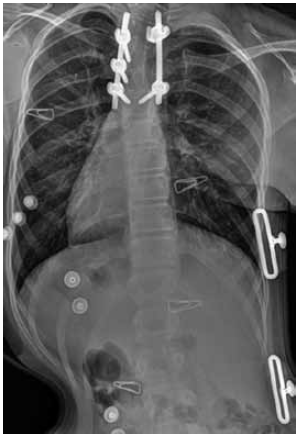

After 4 months, a follow-up examination reported no complaints. A control radiograph of the spine with spinal support, in standing frontal view, was performed. The position of the surgical hardware was radiologically stable and correct. There was no loss of the achieved correction. In addition, there was a right-sided scoliotic arch Th7–Th10 of magnitude 9°, and a left-sided scoliotic arch L1–L4 of 12°, according to Cobb (Fig. 3).

Fig. 3. Radiographs of the spine of the patient F., 11 years old, after surgical treatment, in a spinal support